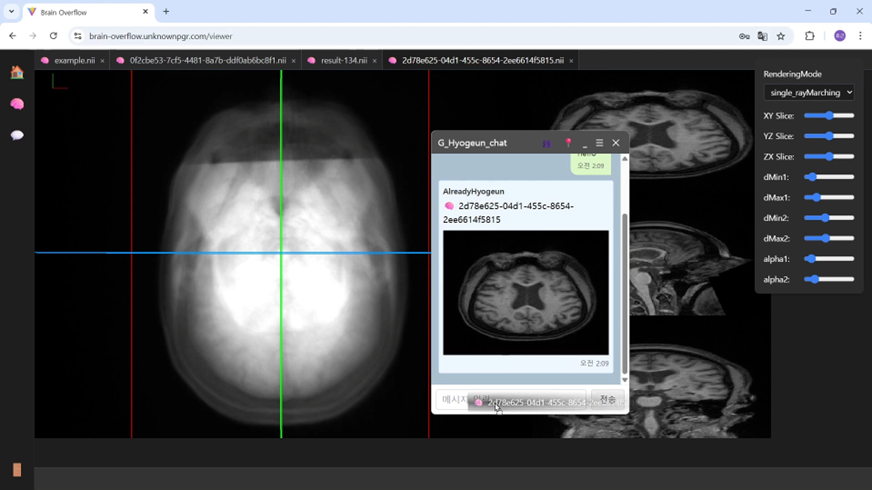

예측 결과가 준비되면, 사용자에게 실시간 알림 팝업으로 “MRI 생성 완료” 메시지가 전송되며, 생성된 MRI는 기존 MRI와 함께 WebGPU 기반 뷰어에서 시각화된다. 사용자는 이 뷰어에서 XY/YZ/ZX 슬라이스를 자유롭게 조정하거나, 여러 렌더링 모드를 통해 입체적으로 뇌 내부 구조를 탐색할 수 있다.

또한, 좌측의 채팅 영역에서는 등록된 사용자와의 그룹 채팅 기능을 지원하며, 탭을 통해 다른 사용자를 초대하거나 대화 중에 MRI 결과 파일을 직접 공유하는 것도 가능하다. 공유된 MRI는 바로 클릭하여 뷰어에서 확인할 수 있도록 연동되어 있다.